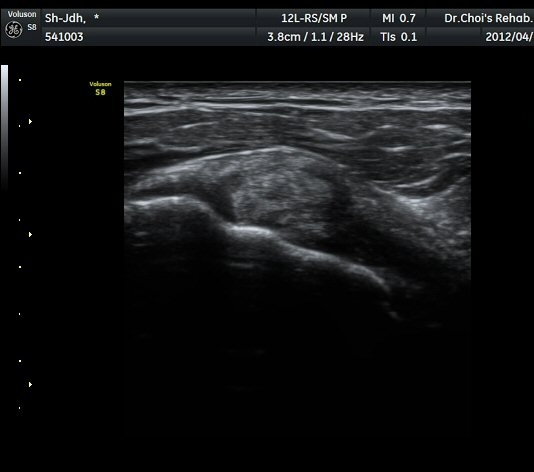

À̵ιڱ٠Ⱦ´Ü¸é°Ë»ç¿¡¼­ À̵ιڱٰÇÀÇ ºñÈĸ¦ º¸ÀÓ(»çÁø 1, 2).

À̵ιڱٰú ÀÌ¿ôÇÑ °ß°©ÇÏ±Ù°Ç »óºÎ¿¡¼­ ±¹¼ÒÀûÀÎ ¿¬°á¼º ¼Ò½ÇÀÌ °üÂûµÊ(»çÁø 3).

¾î±ú µÚ °üÀý¼ø °Ë»ç¿¡¼­ °üÀý¼ø Ç¥Ãþ¿¡ Àú¿¡ÄÚ ¼ö¾×Àú·ù°¡ °üÂûµÊ(»çÁø 4).

ŽÃËÀÚ¸¦ Á» ´õ µÚ·Î À̵¿ÇÏÀÚ °üÀý¼ø ³»Ãø °¡½Ã°üÀý¿À¸ñÆÐÀÓ(spinoglenoid notch)¿¡

¿øÇü¸ð¾çÀÇ Àú¿¡ÄÚ ³¶Á¾ÀÌ °üÂûµÊ(»çÁø 5, 6).